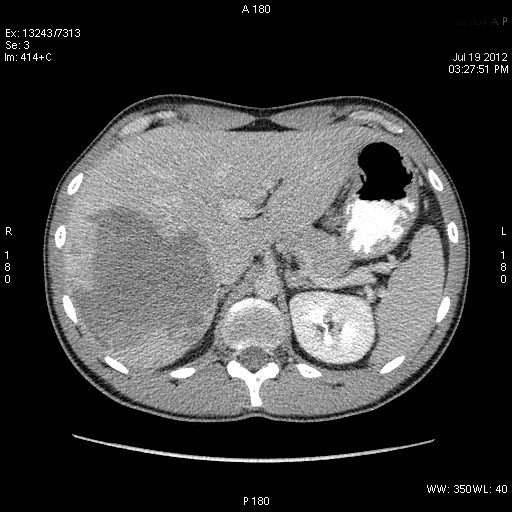

КТ через день

После КТ хирурги заказали дренирование "абсцесса".

Выполнена диагностическая пункция из 4х участков, получена только кровь.